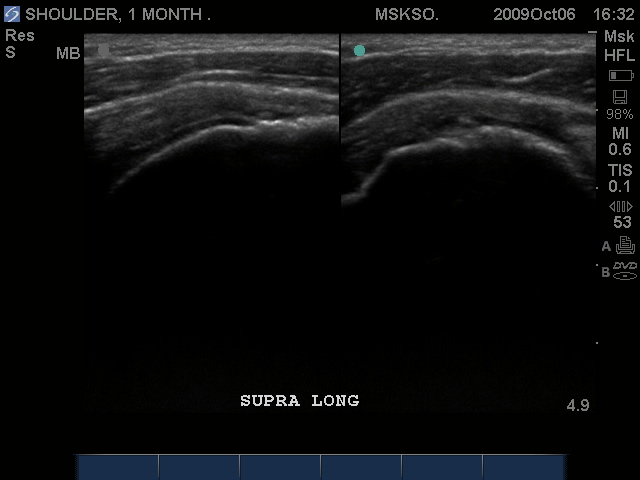

Long axis Supraspinatus tendon over lateral Greater Tuberosity. (lateral greater tuberosity is flat relative to the anterior) Tendon retraction is seen over cartilage interface sign of the humeral head.

Slightly anterior movement of the probe to visualize the full detail of the tear only for this case study purpose.